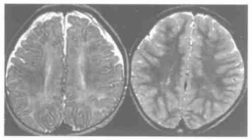

图5.24周BH4D患儿,左图T2WI示双侧侧脑室前后角和体部可见异常高信号。右图为该患儿治疗1年后T2WI上异常高信号消失[2]